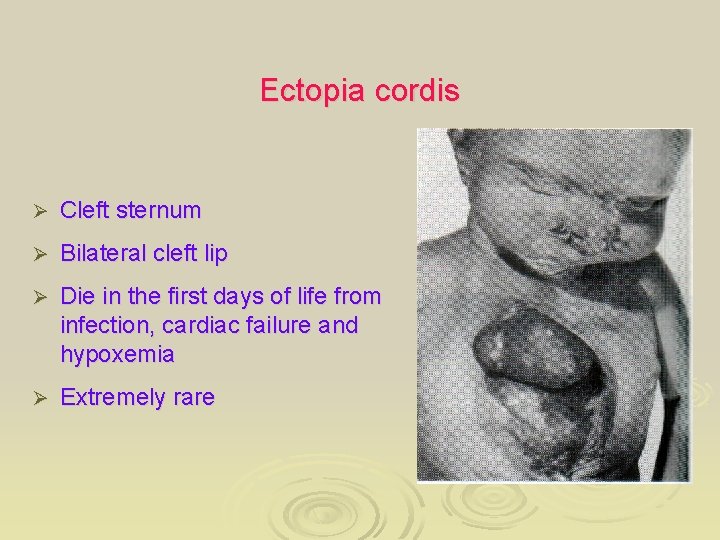

Ectopia cordis Ø Cleft sternum Ø Bilateral cleft lip Ø Die in the first days of life from infection, cardiac failure and hypoxemia Ø Extremely rare